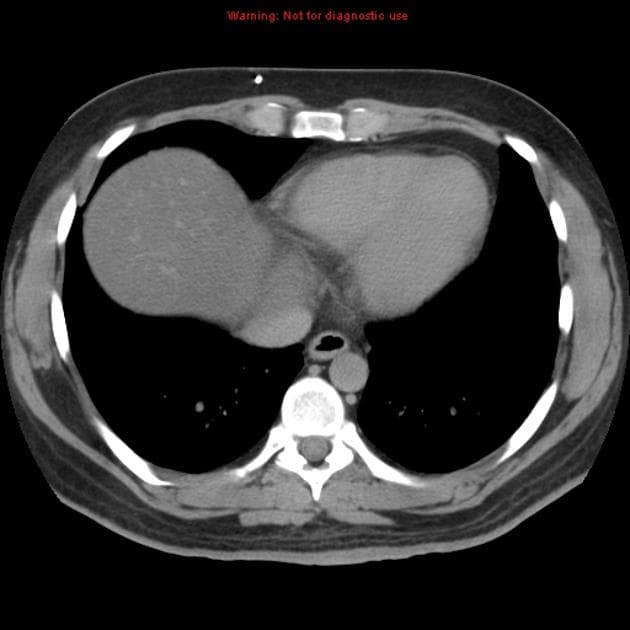

Bệnh nhân đã từng được phẫu thuật cắt bỏ u mạch thần kinh đệm (hemangioblastoma) ở tủy sống, gây ra tình trạng bàng quang thần kinh (lưu ý hình ảnh cắt lớp ngang T2 cho thấy dấu hiệu của phẫu thuật cắt mảnh cung (laminectomy) vùng ngực và các thay đổi tại tủy sống).